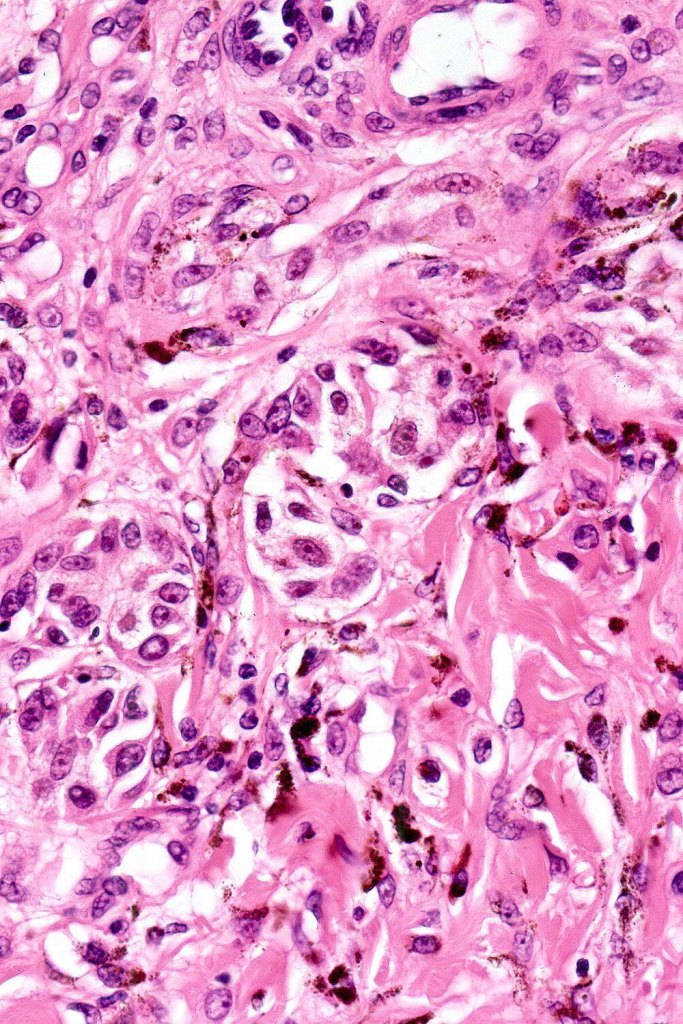

•Symmetrical, circumscribed wedge-shaped infiltrate-most common growth pattern with the broad base uppermost, deeper aspect extends along appendageal structures & neurovascular bundles with a fasciular or plexiform pattern

•Plexiform growth pattern very occasionally seen (plexiform spindle cell nevus (Barnhill)

•Clear cells

•Melanophages

•Multinucleate giant cells